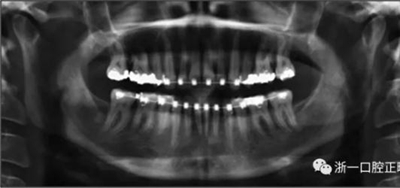

擴(kuò)弓保持8周后,除擴(kuò)弓器影響牙外粘接托槽,使用0.014鎳鈦絲進(jìn)行排齊、整平。旋轉(zhuǎn)停止后3個(gè)月拆除擴(kuò)弓器,全口粘接托槽,使用0.016niti繼續(xù)排齊整平。佩戴可摘保持器,保持上頜寬度。在使用至0.018x0.018niti7周,徹底排齊整平后,使用大弓型的0.016x0.022不銹鋼絲,繼續(xù)維持原有寬度,同時(shí)停止使用可摘保持器。掛II類(lèi)牽,糾正磨牙關(guān)系,使用鏈圈關(guān)閉散在間隙,少量使用IPR去除局部前牙的黑三角。術(shù)后9個(gè)月拍全景示,牙根平行度可,再無(wú)其他牙根出現(xiàn)問(wèn)題。1年7個(gè)月后治療結(jié)束。上下頜3-3舌側(cè)保持器+哈雷氏保持器進(jìn)行保持。